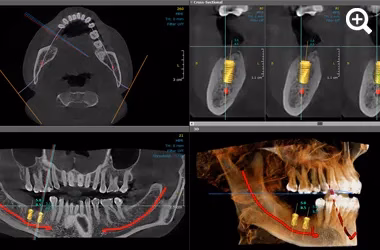

Our digital implant dentistry service in Formby uses CBCT imaging, advanced 3D scans and guided implant placement to deliver precise, comfortable and predictable results.

This stage of digital implant dentistry ensures every implant is positioned safely based on your unique anatomy, using 3D mapping and modern guided techniques.

CBCT and 3D imaging allow exact implant positioning for stable, long-term results.

Your implant journey begins with detailed bone analysis using CBCT and high-resolution 3D scanning.

We plan each implant digitally to achieve the ideal position, angle and depth.